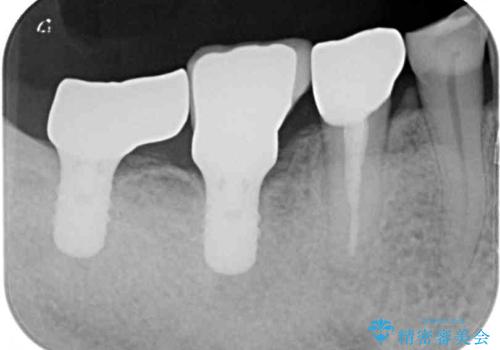

- 強い咬合力により表面のセラミックが剥がれ、裏打ちの金属が見えてしまっていることを気にして来院された患者様です。

仮歯に変えた後、咬合力に耐えることを目的に強化セラミッククラウンにて補綴することとしました。

歯肉が退縮したことで見えていた歯根もセラミッククラウンで覆うことができ、清掃性も改善されました。